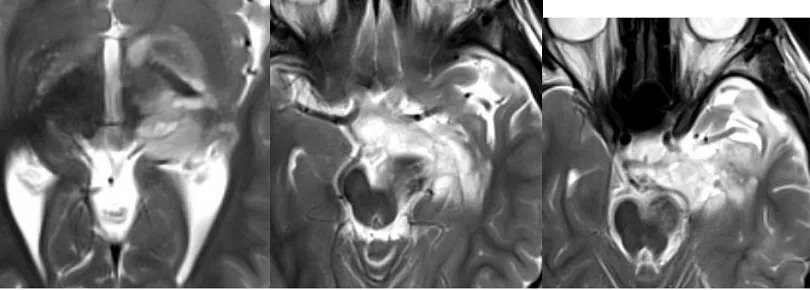

术后3年复查无复发

术后情况:手术1年多后,复查核磁显示肿瘤的切除效果非常理想,局部血管及其他重要结构均得到完整保留。巴教授也为小欧如今的状态感到高兴。如今,小欧的癫痫发作频率明显减少,在随访时,他还可以用流利的英语与巴教授对话,像一个“小大人”般描述自己目前的身体状况,聪明又懂事,令一旁的父母深感欣慰。